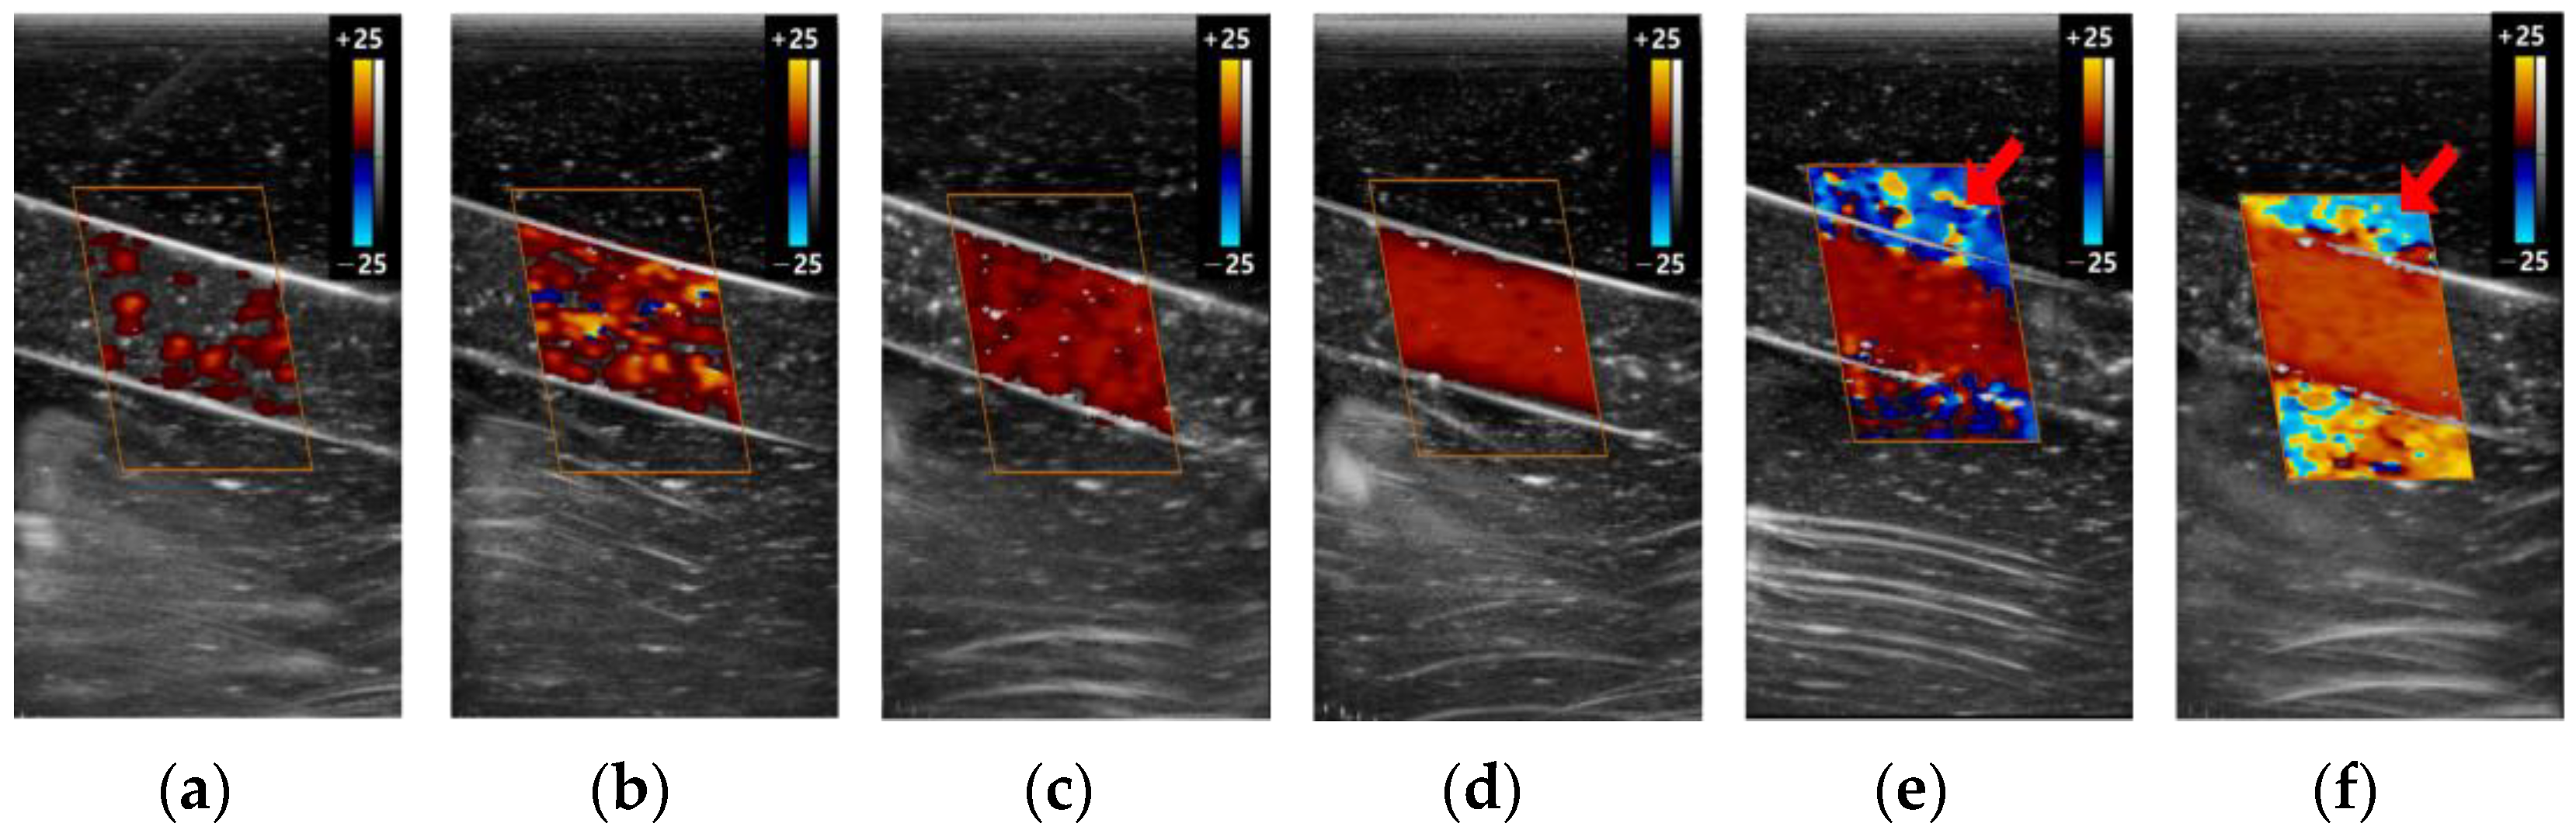

3.2. The Color Doppler Results

3.2.3. Gain